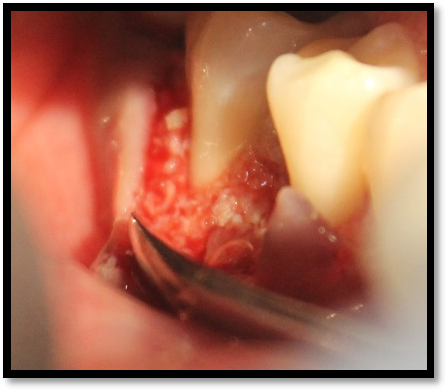

A prospective pre and post interventional comparative study involving patients with a clinical diagnosis of moderate-to-severe chronic periodontitis is being carried out in the department of periodontitis. Inclusion criteria included presence of a 3-walled infrabony defect (IBD) ≥ 3 mm deep in which depth is measured radiographically from the alveolar crest to the base of defect on an intraoral radio-visiographical (RVG) periapical radiograph and the architecture of the 3-walled IBD is confirmed upon surgical exposure of the defect.

Patients are taken up for phase-I therapy which includes thorough supragingival and subgingival scaling and root planning. On re-evaluation after 4-6 weeks of initial therapy full mouth Plaque Index (PI) are recorded and treatment is planned only if the PI is <1.5. Sites for surgical procedure are selected and stents are fabricated for recording of clinical parameters.

Platelet rich fibrin is prepared by taking 10ml of patient’s intravenous blood from median cubital vein in a vaccutainer. Vaccutainer with patients’ blood will be centrifuged at 3000 rpm for 10 minutes by using centrifugation machine.After flap reflection adequate defect debridement and root planning is performed using ultrasonic instrumentation and area-specific curettes. PRF with the bone graft are filled into the IBD.